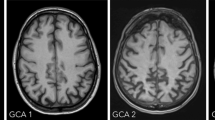

It is well known that glucose represents the source of energy for the brain and that cerebral neuronal activity is tightly coupled to the uptake and metabolism of glucose, probably mediated by the glial cells [14]. Consequently, regional cerebral uptake of [18F]FDG as a tracer for measuring glucose metabolism reflects neuronal function or dysfunction. It has been demonstrated by numerous studies – including studies with in vivo versus postmortem histopathological cross evaluation – that typical patterns of hypometabolism can be observed in manifest neurodegenerative forms of dementia [15]. In Alzheimer’s disease, a characteristic pattern of hypometabolism in the temporoparietal, posterior cingulate, and later also frontal cortex can be observed [16]. The pattern of affected brain regions fits to the functional abnormalities which are usually involving memory, language functions, visual-spatial abilities, and later personality changes. The sensorimotor regions as well as the primary visual cortex and cerebellum are usually spared from metabolic changes, in correspondence with maintained motor and sensory functions in these patients. The topography of these hypometabolic changes is highly specific for Alzheimer’s disease, and it has been demonstrated that FDG-PET allows more accurate diagnosis as compared to neuropsychological assessment [17]. Importantly, hypometabolic abnormalities are not only observed in patients with manifest dementia of Alzheimer’s type but also in earlier stages of disease. A number of studies analyzed the value of FDG-PET in the early detection of Alzheimer’s disease in the stage of MCI. It has been demonstrated that mild hypometabolism in posterior cingulate cortical regions, often accompanied by subtle parietal and temporal hypometabolism, has a high predictive value with regard to later conversion to manifest dementia in these patients [16, 18]. On the other hand, patients with MCI symptoms but without signs of hypometabolism on FDG-PET have a very low risk of conversion to dementia of Alzheimer’s type. FDG-PET has also been demonstrated to have a very high value in the differential diagnosis between different forms of neurodegenerative disorders [19]. For non-Alzheimer forms of dementia, disease-specific patterns of hypometabolism have been described. Dementia with Lewy bodies has been shown to be associated with a pattern of temporoparietal hypometabolism similar to Alzheimer’s disease, however, extending clearly into the occipital cortex, involving primary visual cortical areas [20]. This goes hand in hand with the known visual hallucinations in these patients. FDG-PET has also been shown to have a high value for differentiation between Alzheimer’s-type dementia and the frontotemporal lobar degenerative disorders [21]. Also, for the different subtypes of frontotemporal lobar degeneration (FTLD), specific patterns of hypometabolism have been described [22–27], with the behavioral variant (bvFTD) showing stronger frontal and temporal polar abnormalities [28], the semantic variant of primary progressive aphasia (svPPA) displaying bilateral temporal hypometabolism [25, 29, 30], and the logopenic variant as well as the nonfluent variant (lvPPA, nfvPPA) both demonstrating clearly asymmetric unilateral (usually left-hemispheric) hypometabolism of the temporal and in part frontal and parietal cortex. In nfvPPA, involvement of left frontal cortical regions (often including Broca’s area) has been shown [31, 32], and in lvPPA hypometabolic regions have been observed within the left lateral temporal and parietal lobe as well as in the precuneus and posterior frontal lobe [33–36]. It has to be mentioned that the FDG pattern is reflecting the symptomatic appearance of these subtypes of neurodegeneration without allowing a clear distinction of the underlying neuropathology. FTLD has been demonstrated to comprise a number of different causal pathologies which can result in similar clinical phenotypes of disease [37, 39]. This includes tau-positive forms, TDP-43 aggregation-positive forms, and even atypical forms of Alzheimer’s disease. In particular the variant of logopenic aphasia has been demonstrated to frequently represent an atypical variant of Alzheimer’s disease [31]. However, other neuropathological changes such as TDP-43 may result in the clinical appearance of lvPPA accompanied by a similar hypometabolic pattern in FDG-PET [33]. In addition to the phenotype of logopenic aphasia, Alzheimer’s disease can appear in other atypical variants. This includes the so-called posterior cortical atrophy, which is characterized by predominantly visual-constructive deficits in the early phases of disease, often leading the patients to see an ophthalmologist [39]. In the FDG-PET scan these patients exhibit a distinct bilateral occipitoparietal hypometabolism [40, 41]. Another atypical form of Alzheimer’s disease is the frontal/executive subtype [42]. Patients may show symptoms more similar to the behavioral variant of frontotemporal dementia in early cases. In the FDG-PET scan, they show frontal cortical hypometabolism, but in contrast to bvFTD usually some involvement of temporoparietal cortices is to be expected. Using amyloid imaging (see below) doubts about the causal pathology in these atypical cases of Alzheimer’s disease can be cleared. Finally, FDG-PET represents a valuable tool to differentiate pseudodementia in patients with depression and cognitive symptoms (who will show a rather normal finding on the FDG-PET scan) versus patients suffering from early Alzheimer’s disease with depressive symptoms [43].